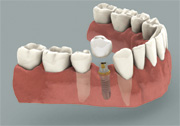

Implant with a crown

Missing a tooth ? An Implant can replace that missing tooth in no time. Modern dental implants are precision devices, the most common type is a titanium screw that is anchored into the jawbone where it serves as post for a custom-made tooth crown. Once the crown is in place, you may not be able to tell it apart from your natural teeth.